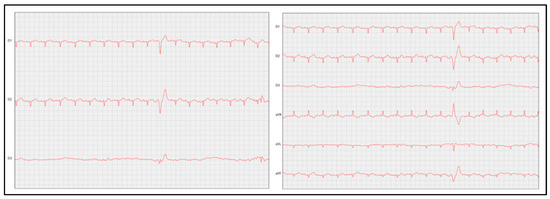

Clinical-Diagnostic and Therapeutic Advances in Feline Hypertrophic Cardiomyopathy

by Felipe Gaia de Sousa, Ana Cristina Ribeiro Mendes, Luisa Pimenta de Carvalho and Suzane Lilian Beier

Vet. Sci. 2025, 12(3), 289; https://doi.org/10.3390/vetsci12030289 - 19 Mar 2025

Cited by 3 | Viewed by 20325

A comprehensive literature review was conducted to summarise existing evidence and the latest therapeutic advancements in feline HCM. The disease phenotype is characterised by the development of concentric hypertrophy, which is variable but often asymmetric, primarily affecting the left ventricle. The HCM is [...] Read more.

A comprehensive literature review was conducted to summarise existing evidence and the latest therapeutic advancements in feline HCM. The disease phenotype is characterised by the development of concentric hypertrophy, which is variable but often asymmetric, primarily affecting the left ventricle. The HCM is marked by diastolic dysfunction, resulting in a reduced intracavitary internal diameter due to the disordered alignment of cardiomyocytes and excessive collagen deposition, which thickens the myocardial tissue and impairs relaxation. There is strong evidence supporting the role of genetic mutations in sarcomeric genes in the development of HCM. Clinical signs vary but are frequently associated with congestive heart failure (CHF) and ATE. Diagnosis is based on a combination of clinical evaluation, laboratory tests, and imaging studies, although certain aspects of the disease remain insufficiently understood and require further research. Therapeutic management focuses on controlling clinical signs, slowing disease progression, and improving both quality of life and life expectancy. However, ongoing studies are essential to refine diagnostic strategies and explore novel treatment options for better disease management. Full article